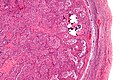

Gondaloblastoma. H&E stain. | |

| LM | immature germ cells (resembling Sertoli cells or granulosa cells),[citation needed] primitive germ cells resemble those of a dysgerminoma, +/-calcification (very common), +/-eosinophilic basement membrane material between the (primitive) germ cells and support cells. |

Gonadoblastoma is a rare germ cell tumour with sex cord elements.

- A mixed tumour that consists of (1) primitive germ cells and (2) sex cord elements.

Features:[1]

- Immature germ cells resembling Sertoli cells or granulosa cells.[citation needed]

- Sertoli cells = moderate cytoplasm in a trabecular or tubular architecture.

- Granulosa cells = form follicle-like structures.

- May form nests.

- Primitive germ cells resemble those of a dysgerminoma.

- Polygonal cells with a central nucleus, squared-off nuclear membrane and clear cytoplasm.

- +/-Calcification (very common).

- +/-Eosinophilic basement membrane material between the (primitive) germ cells and support cells.[2]